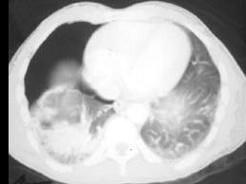

男,31岁,车祸后10小时余,请结合影像学检查,选出最可能的诊断 ( )A、矽肺B、大叶性肺炎C、肺结核D、气胸伴肺挫伤E、肺癌

问题 男,31岁,车祸后10小时余,请结合影像学检查,选出最可能的诊断 ( )

选项 A、矽肺 B、大叶性肺炎 C、肺结核 D、气胸伴肺挫伤 E、肺癌

答案 D